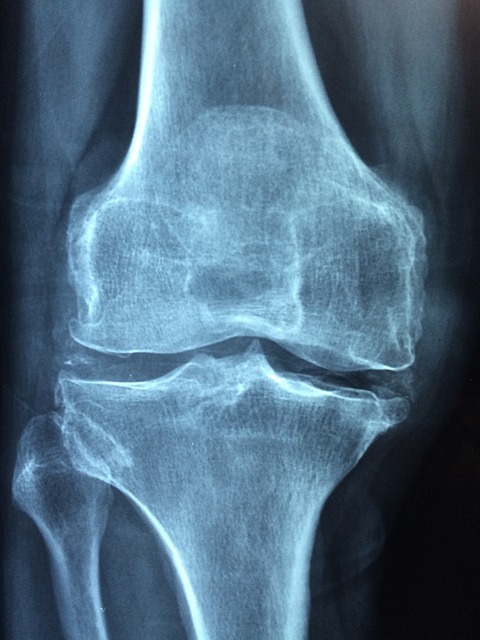

골다공증은 뼈를 약화시켜 뼈가 약해지고 골절되기 쉽게 만드는 질환입니다. 쉽게 말하면 단단한 뼈이 아니라 스펀지 같은 뼈를 갖고 있는 셈이다. 불행하게도 뼈가 부러지기 전까지는 눈에 띄는 증상이 나타나지 않는 경우가 많습니다. 그러나 일부 경고 신호는 다음과 같습니다.

- 골절: 뼈가 너무 약해져서 작은 충격이나 넘어짐에도 골절이 발생할 수 있으며, 특히 엉덩이, 척추, 손목 부위가 더욱 그렇습니다.

골다공증은 뼈의 밀도가 감소하고 부서지기 쉬울 때 발생합니다. 골다공증의 주요 원인은 다음과 같습니다.